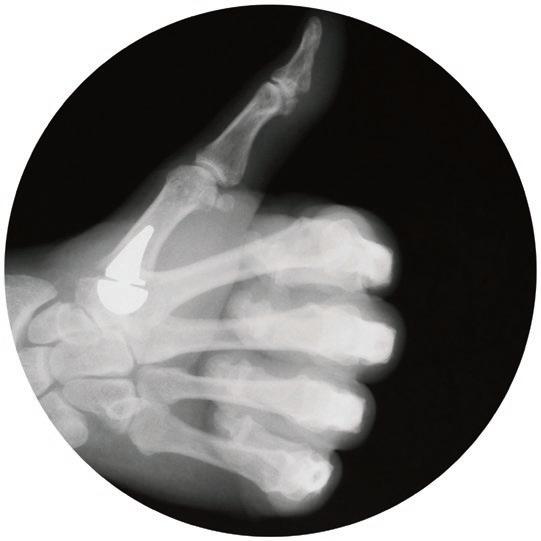

Thumbs Up!

Antony Hazel, MD, hand specialist at Norton Arm & Hand Institute, specializes in unique thumb surgery

LOUISVILLE People commonly ask a friend or neighbor if they know a good handyman. After all, it is always good to know someone who knows how to fix things, such as a leaky faucet or a broken washing machine. But what sort of handyman do you call for an injured hand? If you’re anywhere within 200 miles of Louisville, the answer is likely to be Antony Hazel, MD, orthopedic hand surgeon at Norton Arm & Hand Institute in Louisville.

Hazel treats a variety of upper extremity issues, but is becoming proficient and widely known for a thumb implant procedure that can have a major impact on a patient’s quality of life.

Implant Design: The twopiece implant allows for 48 total configurations, allowing surgeons to customize the fit.

Dr. Antony Hazel prepares a patient for thumb implant surgery. Dr. Hazel is one of only a few in the region who regularly perform this procedure, which is designed for patients with severe arthritis.

What brings people from far and wide, however, is his expertise with thumb implant surgery. The Modular Thumb Implant made by BioPro replaces the damaged joint surfaces

of the basal joint between the wrist and thumb.

“The patient has usually been having a problem for years,” Hazel says of the typical candidate for this procedure. “They have pain at the base of the thumb. They have difficulty pinching or gripping, where the activities of daily living are becoming hard to do. They have exhausted using a brace, they are tired of getting shots, and the shots have a diminishing relief.”

These patients tend to be in their 60s, though Hazel has performed the surgery on those as young as 38. Many are still working and need their hands to successfully do their jobs.

“It’s arthritis. Bone on bone,” Hazel says. “Sometimes the joint can even have subluxation where it’s not dislocated, but it is not sitting in the right spot. Any time they attempt to move it, it can hurt quite a bit.”

That pain becomes debilitating and the thought of relief-delivering surgery becomes more appealing.

“Patients are ready to undergo the surgery when they are tired of dealing with the pain,” Hazel says.

Hazel says the procedure is an improvement over the traditional trapeziectomy, which removes the trapezium bone at the base of the thumb.

“If you’re a younger patient, no one is really excited to do that because with time, you would worry about subsidence, where the first metacarpal basically descends onto the scaphoid,” Hazel says. “If you remove the trapezium in a young person, at some point they may subside causing a new set of issues. That is a difficult problem to handle. The risk of subsidence has always made me nervous about doing a traditional trapeziectomy. The

implant makes a lot of sense because it tries to restore normal anatomy.”

Being the only surgeon who does the BioPro Modular Thumb Implant procedure in an approximate 200-mile radius, Hazel has had patients come from as far as Tennessee, Missouri, Illinois, and Indiana for the procedure. He first performed it eight years ago, and to date he estimates that he has performed about 40 of these surgeries, with a significant increase in the last two years.

“The hardest part of the procedure is creating the socket because there is no template for that,” Hazel says. “We’re still trying to figure out how long the implant can last. Even if it is 10 to 15 years, I feel like that can get people through a big majority of their really active phase of life.”

Though he’s had good success with the procedure, Hazel makes sure that patients understand that is not a pleasant recovery and that nothing is guaranteed.